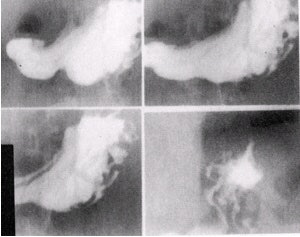

![]() |

| Double-contrast images of duodenal bulb in left lateral position in various obliques (10 x 12 image receptor, 4 on 1). Image courtesy of Dr. Naveed Ahmad. |

- Keep the patient in the right lateral position until the duodenal bulb fills with dense barium, and then turn the patient to the left lateral position. When gas fills the bulb, take images in various obliques.